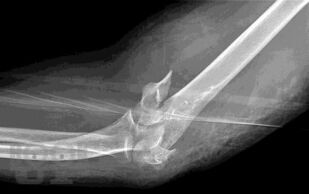

Учебно-практическое издание содержит ситуационные задания по наиболее распространенным и сложным разделам патологии опорно-двигательной системы (повреждения и заболевания верхних и нижних конечностей, позвоночника, повреждения и заболевания детского возраста и остеоонкология). Материал ситуационных заданий основывается на практическом опыте мирового сообщества травматологов-ортопедов. Для удобства восприятия материала эталоны ответов на ситуационные задания расположены в конце каждого задания. Практикум предназначен для ординаторов, аспирантов и врачей травматологов-ортопедов, обучающихся по специальности «Травматология и ортопедия».